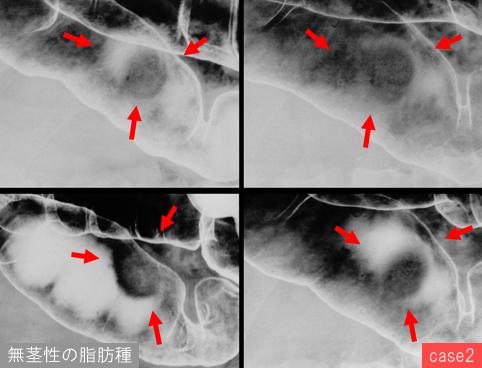

질환(병리주체)의 분류 기타/

부위(장기별) 대장/횡행

검사방법 X-P

종양의 최대경(밀리미터) 25~29